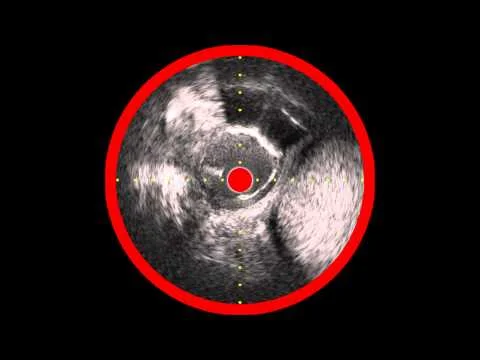

Eagle-Eye IVUS after Mustang PTA of LSFA